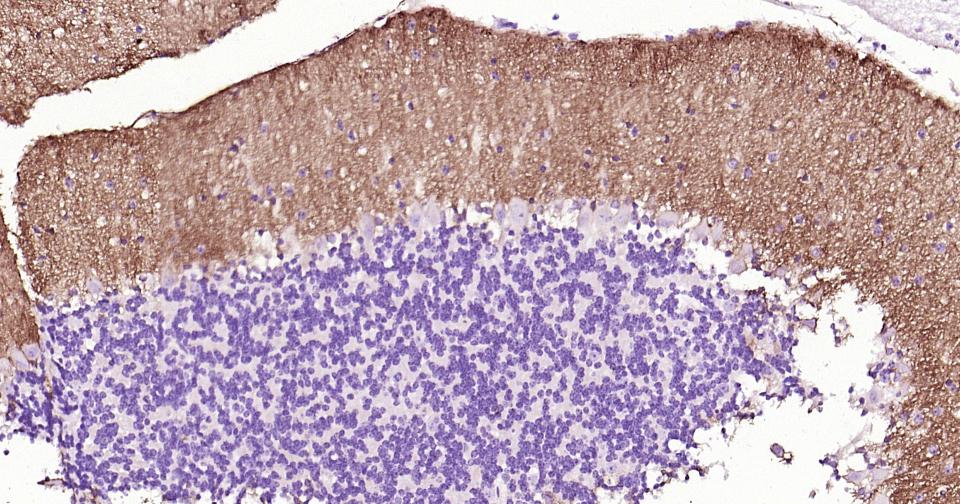

Paraformaldehyde-fixed, paraffin embedded Human Cerebellum; Antigen retrieval by boiling in sodium citrate buffer (pH6.0) for 15 min; Antibody incubation with EAAT1 Monoclonal Antibody, Unconjugated(bsm-60880R) at 1:200 overnight at 4°C, followed by conjugation to the bs-0295G-HRP and DAB (C-0010) staining.